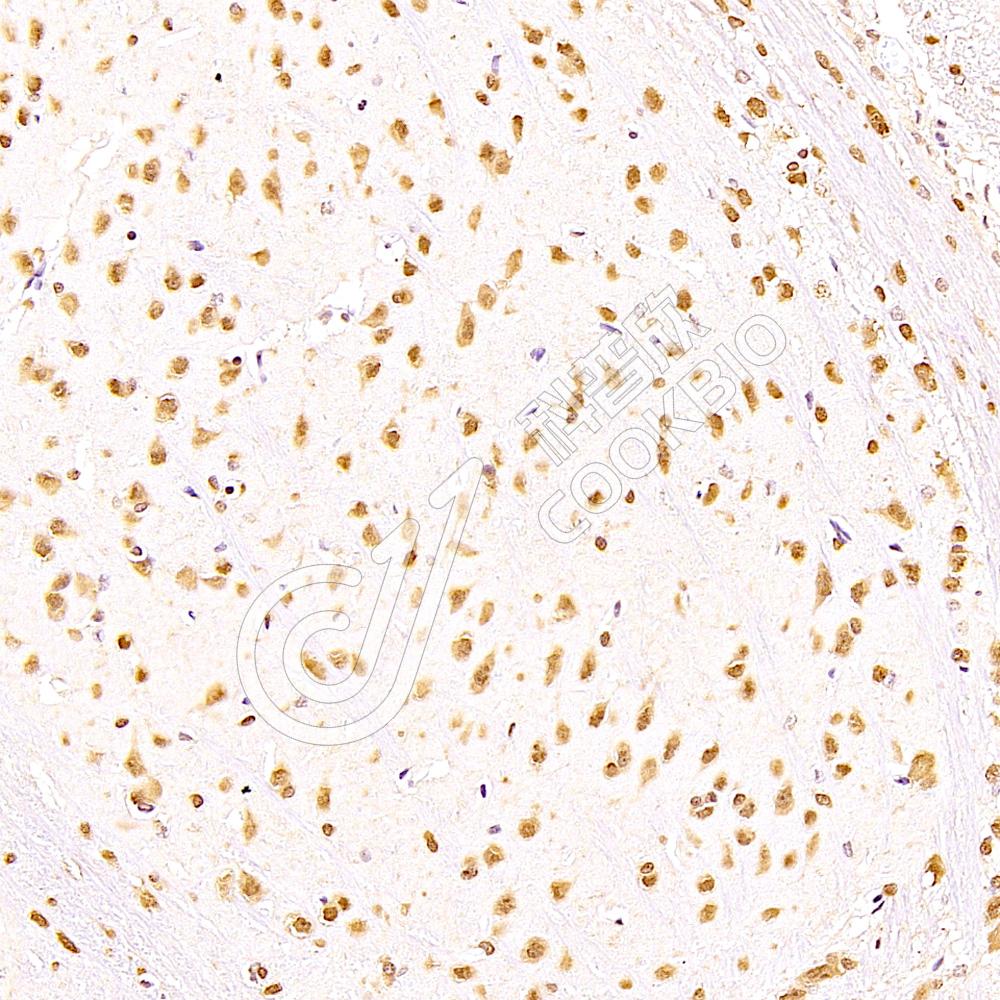

IHC检测ELAVL3蛋白(货号 K1337797).

样品: 小鼠脑, 4%多聚甲醛 (货号KSG1101) 固定12-24小时.

抗原修复: 柠檬酸抗原修复液(干粉, pH 6.0) (KSG1201), 98℃, 20分钟.

—抗: 1: 2100稀释, 4℃ 孵育过夜.

二抗: S-vision免疫组化多聚二抗(山羊抗兔),即用型 (货号KB3906), 室温孵育20分钟.

样品: 大鼠脑, 4%多聚甲醛 (货号KSG1101) 固定12-24小时.